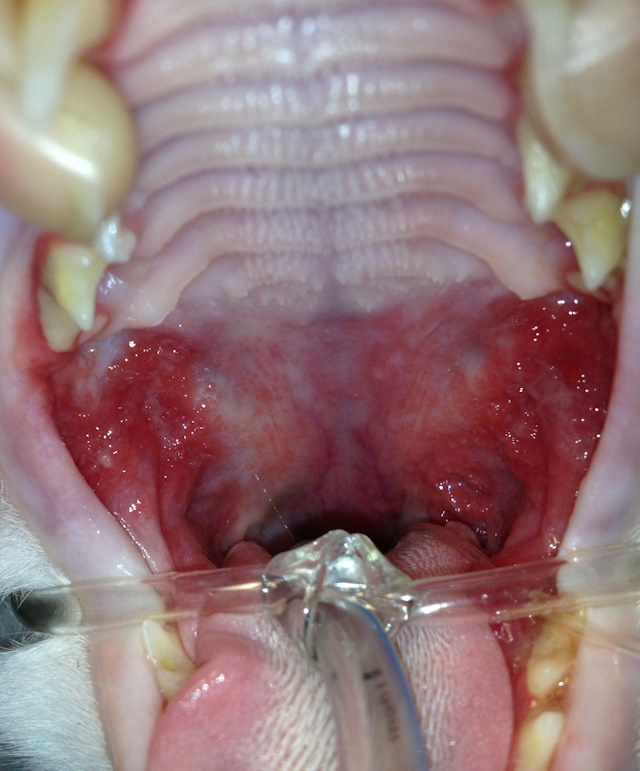

Severe oral inflammatory changes consistent with feline chronic gingivostomatitis (FCGS).

Severe caudal stomatitis. The palatoglossal arches and caudal oral mucosa are intensely erythematous, thickened, and irregular.